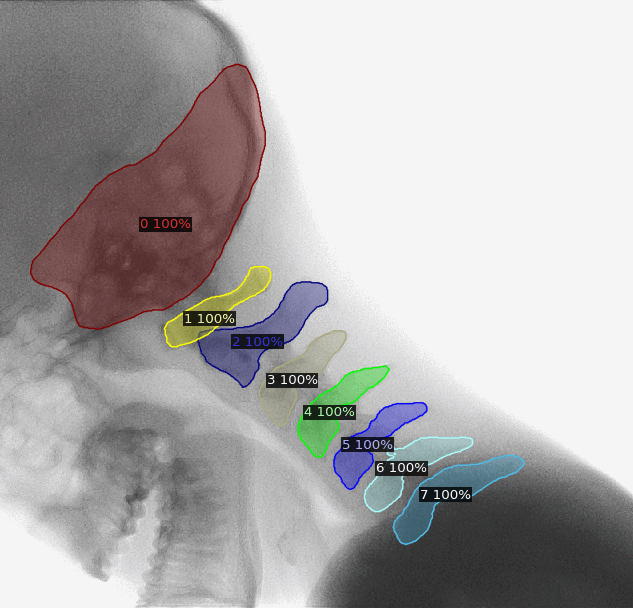

The use of artificial intelligence in diagnostic medical imaging has shown impressive accuracy and sensitivity in the identification of imaging abnormalities. Assisting healthcare professionals with detection, segmentation and classification, it can be of immense value for screenings and precision medicine. Our AI for Health engineers used Generative Adversarial Networks to segment X-rays of lungs to detect Covid-19. They applied U-nets and mask-RCNN for instance segmentation of cervical vertebrae to predict patient developing hernia.